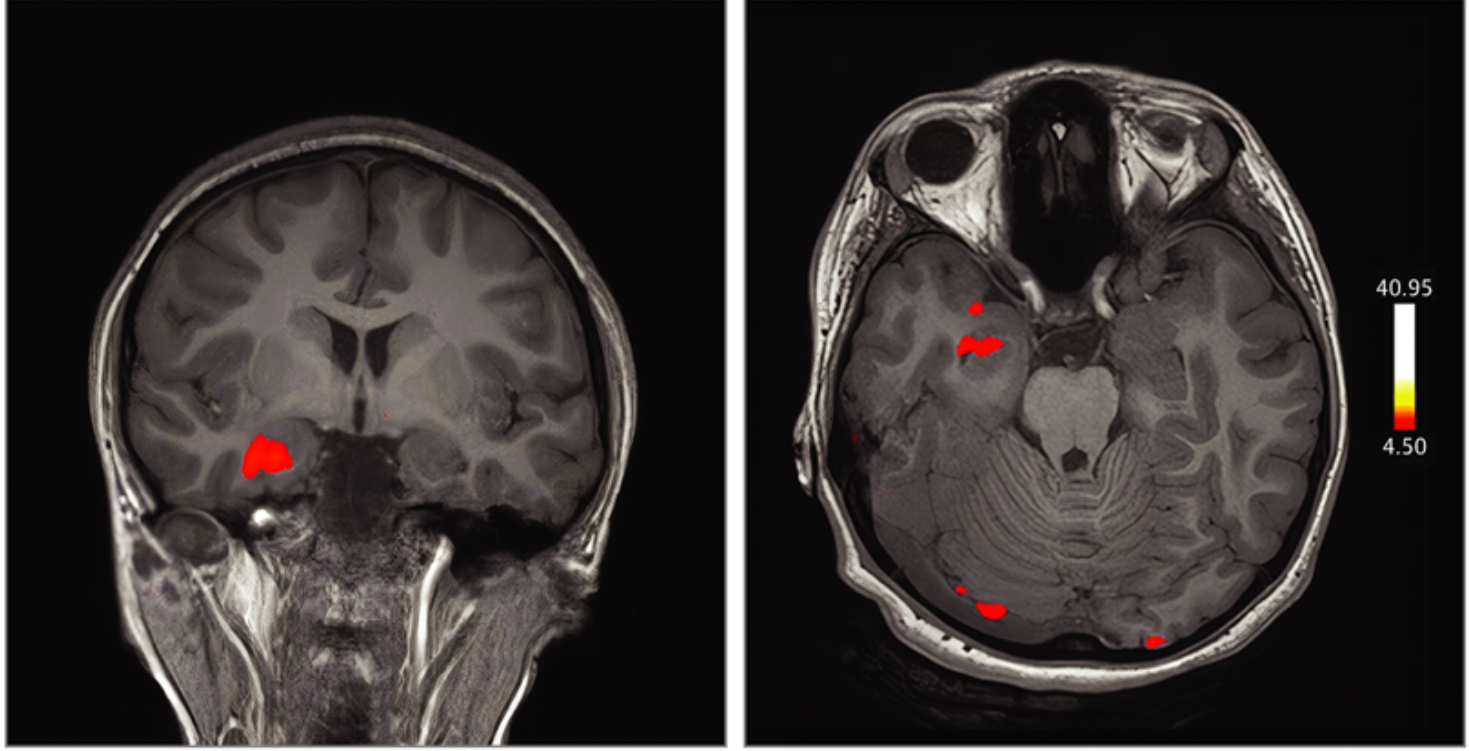

Large numbers of perivascular spaces seen in the brain are more commonly found in patients who go on to develop cognitive problems or dementia.